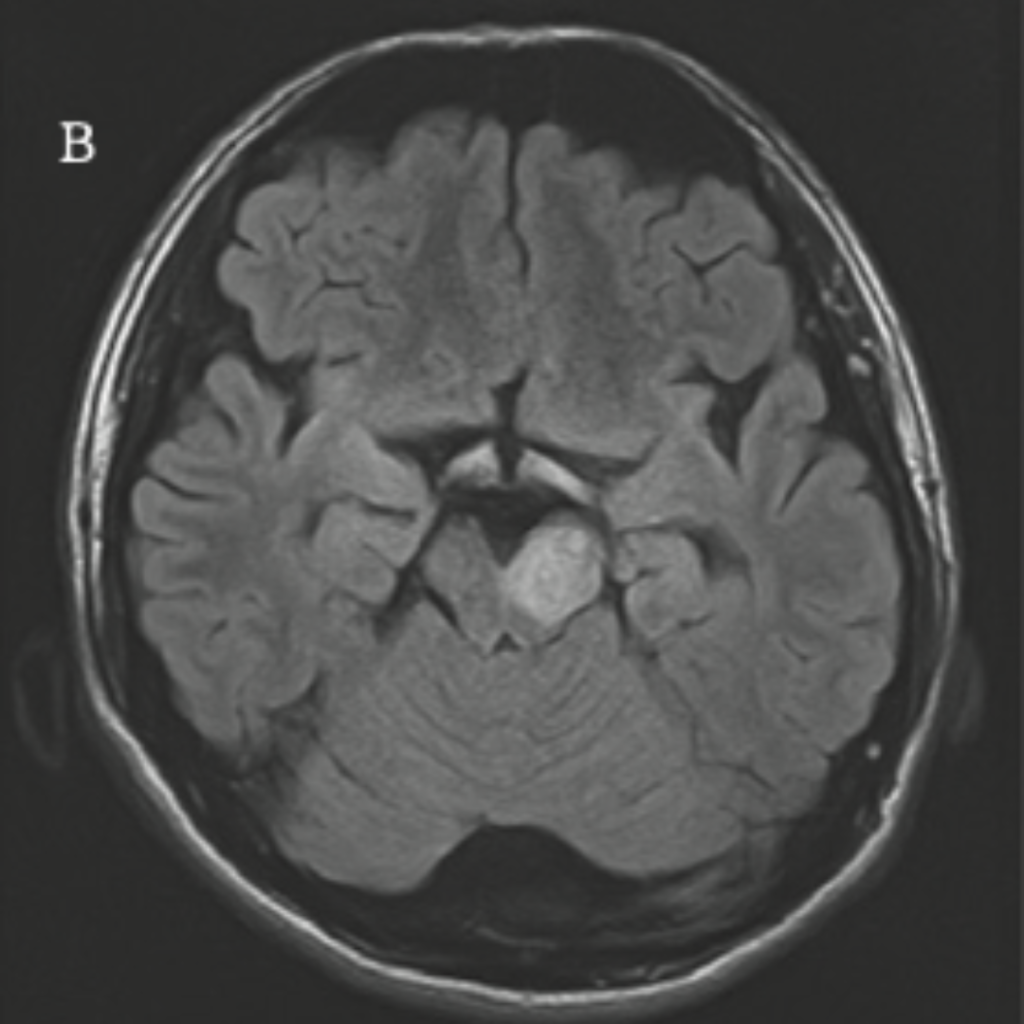

脳や神経に中枢神経ループスと呼ばれる、脳の炎症を認める事が特徴的です。

神経病変、

神経病変:https://www.neurology-jp.org/Journal/public_pdf/051040261.pdf